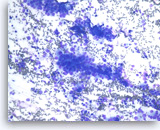

Non-Hodgkin B-cell lymphoma,

Pancreas FNA, Direct Smear.

The aspirates show dispersed single intermediate to large atypical lymphocytes.

20X

Non-Hodgkin B-cell lymphoma,

Pancreas FNA, Direct Smear.

The aspirates show dispersed single intermediate to large atypical lymphocytes.

20X

Non-Hodgkin B-cell lymphoma,

Pancreas FNA, Direct Smear.

At a higher magnification, the atypical lymphocytes show variations in size and shape. Scattered lymphoglandular bodies are seen in the background.

40X

Non-Hodgkin B-cell lymphoma,

Pancreas FNA, Direct Smear.

At a higher magnification, the atypical lymphocytes show variations in size and shape. Scattered lymphoglandular bodies are seen in the background.

40X